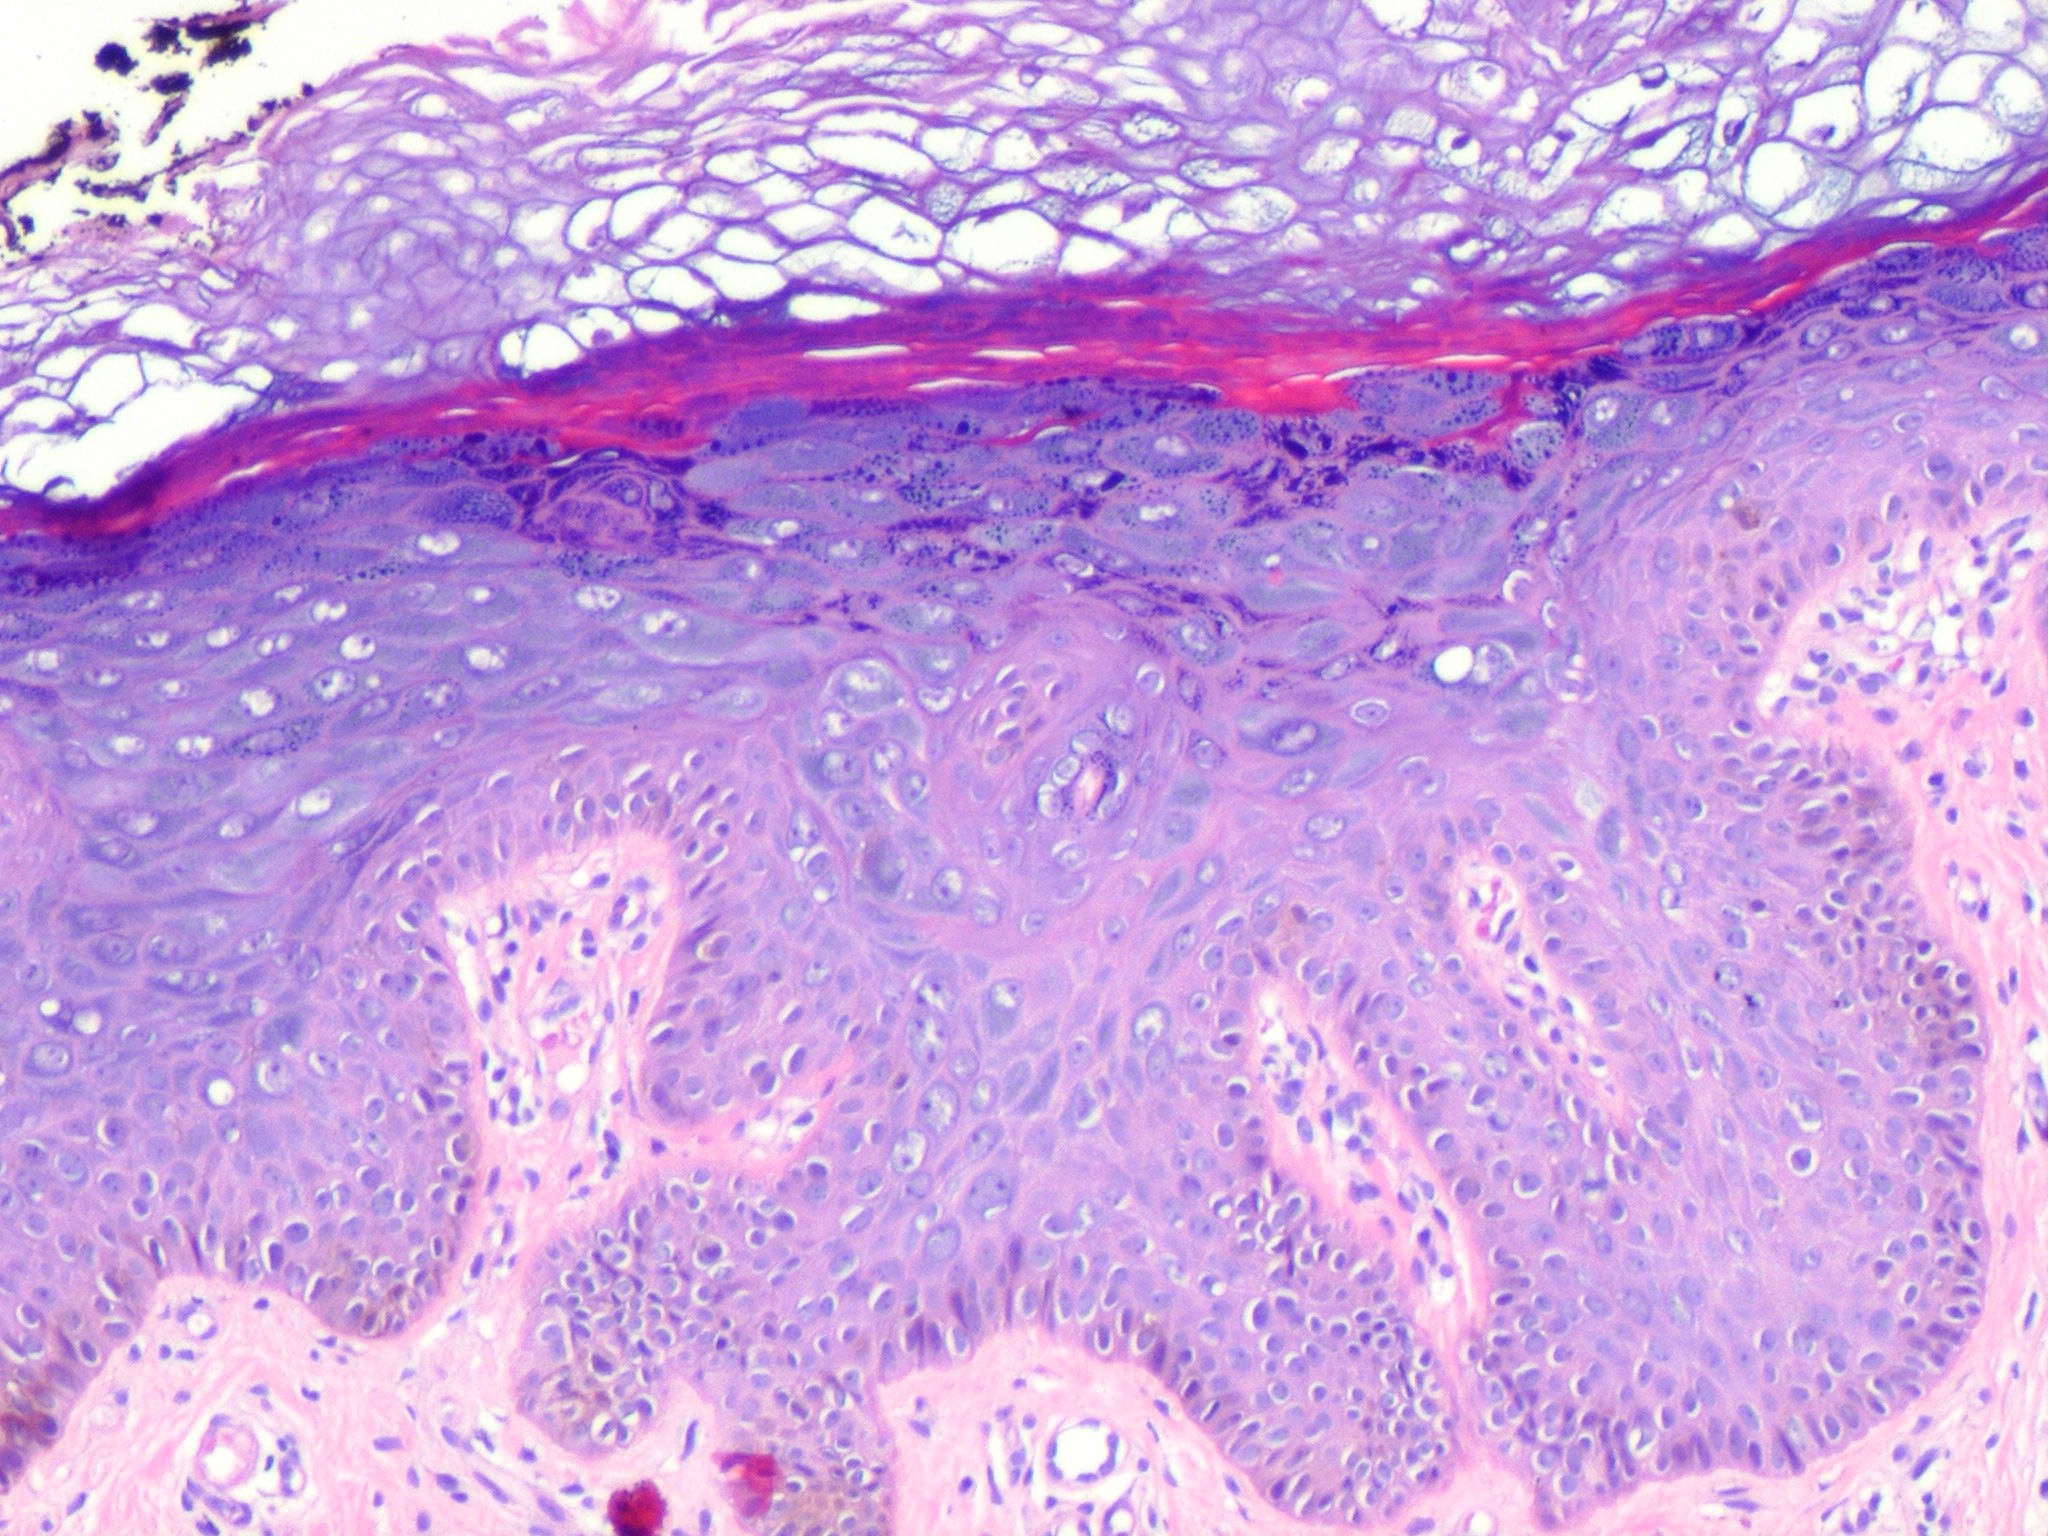

Epidermodysplasia Verruciformis =عسر تصنع البشرة الثؤلولي